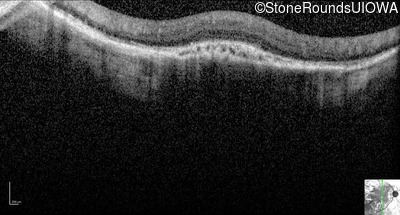

Optical Coherence Tomography - Left - 5/200

Exemplar / OCT Stack

OCT Stack